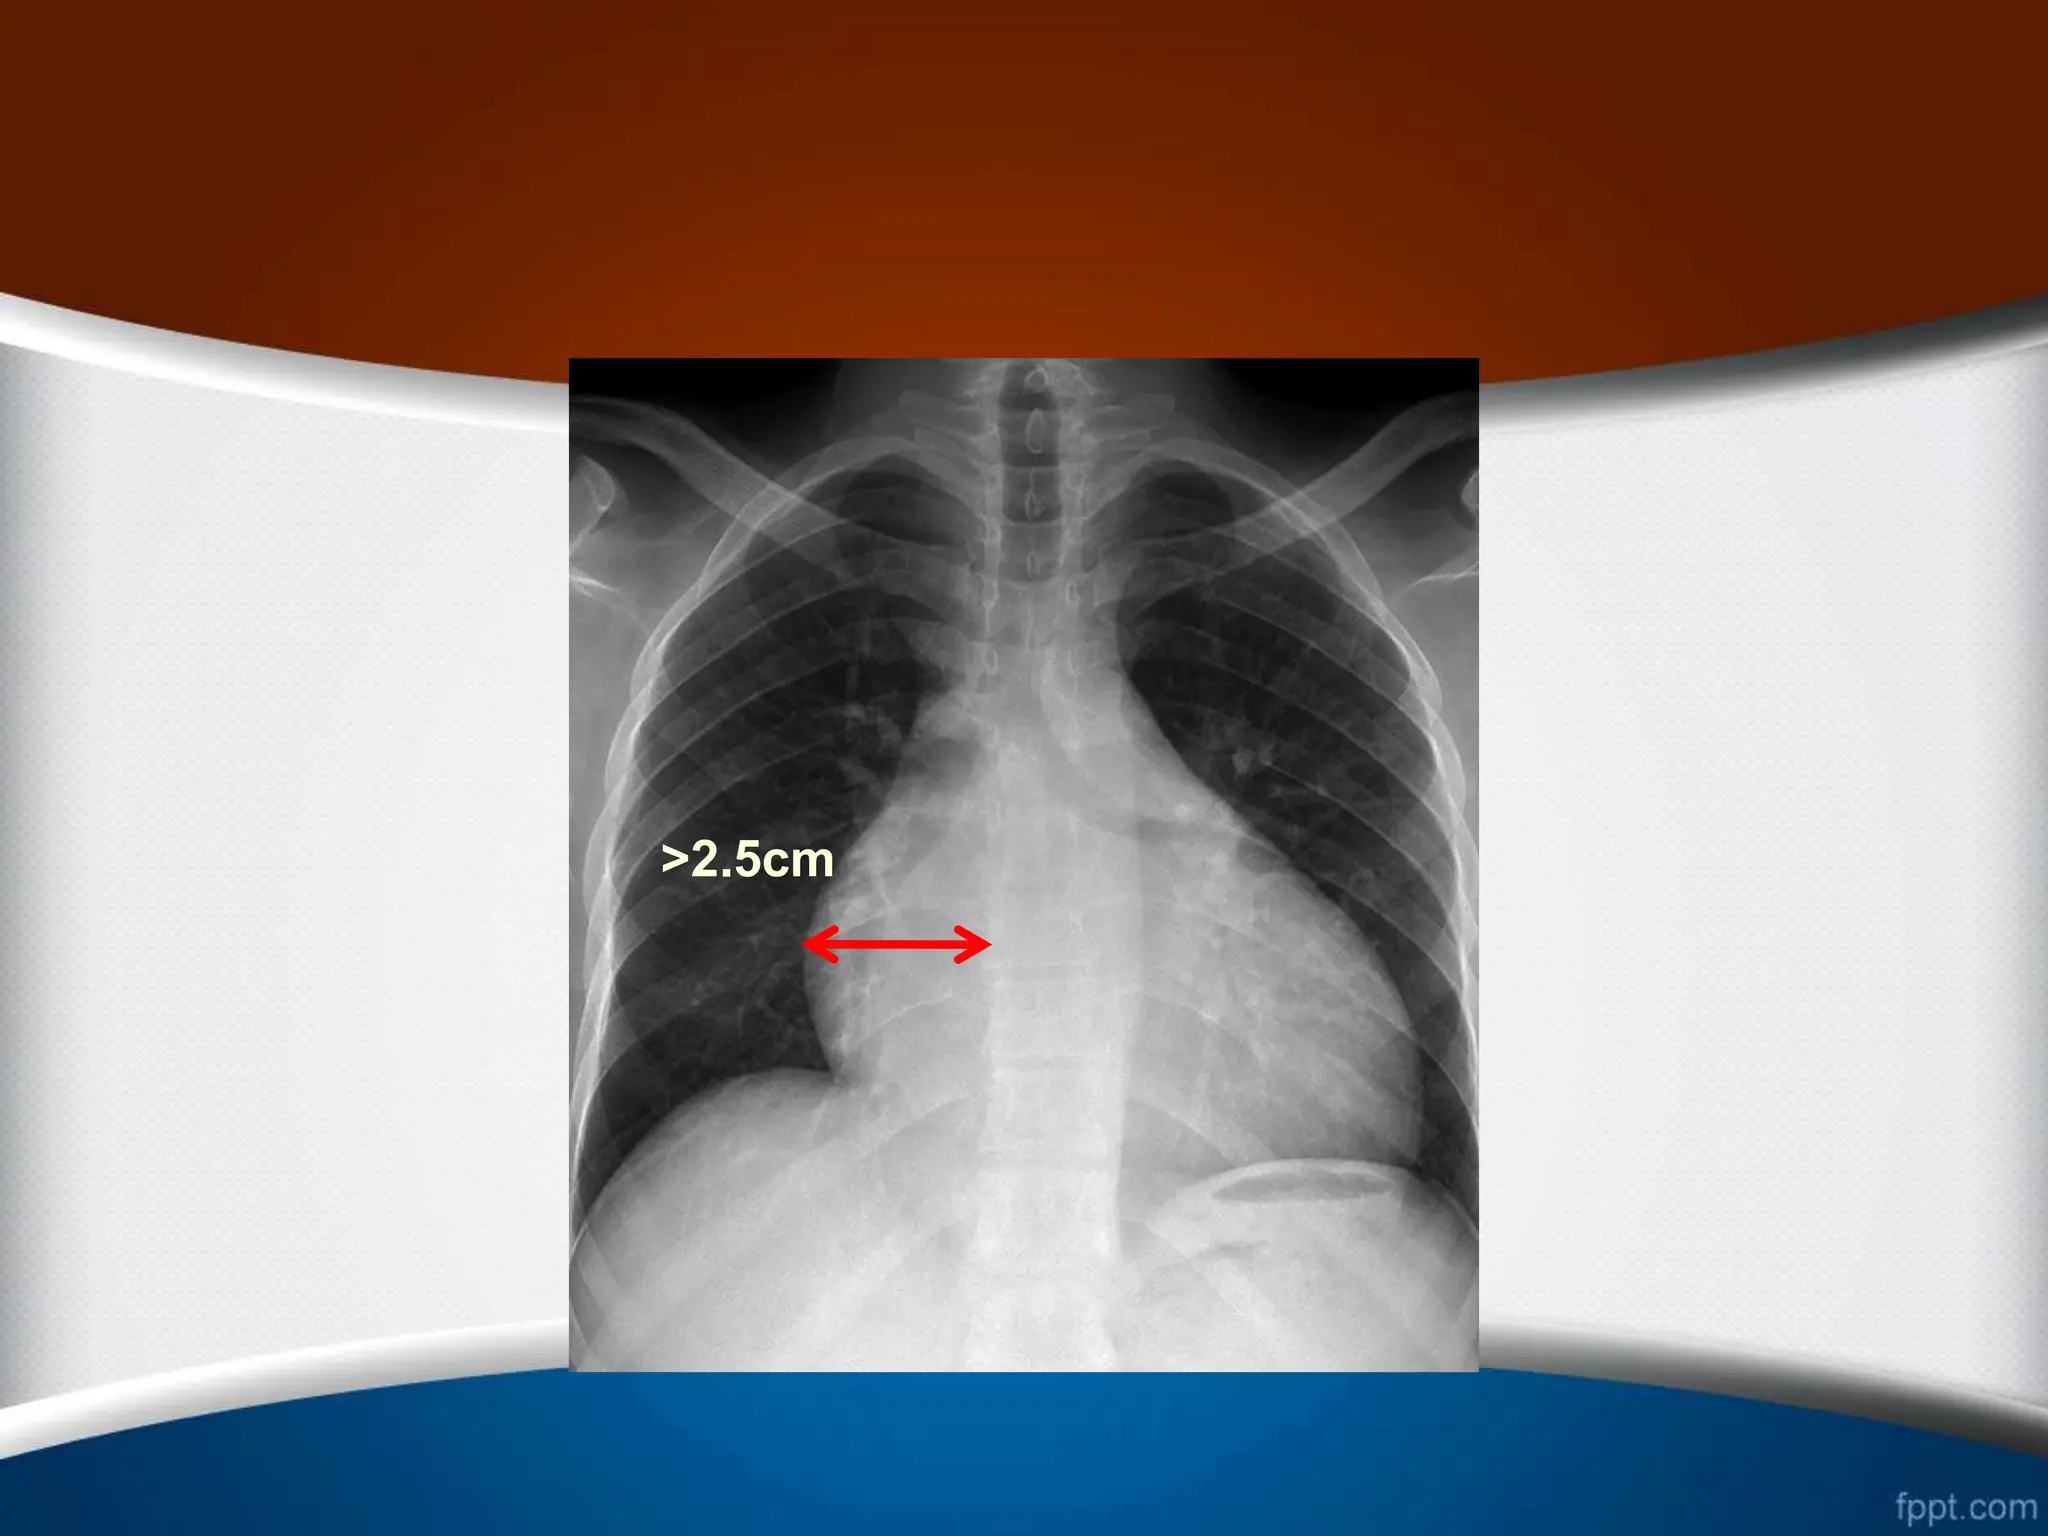

‫راست‬ ‫دهلیز‬ ‫بزرگی‬

‫از‬ ‫بیشتر‬ ‫وسط‬ ‫خط‬ ‫از‬ ‫راست‬ ‫دهلیز‬ ‫ی‬ ‫حاشیه‬ ‫بین‬ ‫ی‬ ‫فاصله‬

5.5

‫از‬ ‫بیشتر‬ ‫ها‬ ‫مهره‬ ‫ستون‬ ‫راست‬ ‫حاشیه‬ ‫از‬ ‫و‬ ‫متر‬ ‫سانتی‬

2.5

‫متر‬ ‫سانتی‬

.

>5.5cm

>2.5cm

>25%

>1/3

‫راست‬ ‫دهلیز‬ ‫بزرگی‬ .1 ‫از‬‫بیشتر‬ ‫قلب‬ ‫راست‬ ‫ی‬ ‫کناره‬ ‫افزایش‬ 25 % ‫قلب‬ ‫عرضی‬ ‫دیامتر‬ .2 ‫راست‬ ‫کاردیوفرنیک‬ ‫ی‬ ‫زاویه‬ ‫شدن‬ ‫باز‬ ( ‫منفرجه‬ ‫یا‬ ‫قائمه‬ ) .3 ‫از‬ ‫بیشتر‬ ‫وسط‬ ‫خط‬ ‫از‬ ‫راست‬ ‫دهلیز‬ ‫ی‬ ‫حاشیه‬ ‫بین‬ ‫ی‬ ‫فاصله‬ 5.5 ‫از‬ ‫بیشتر‬ ‫ها‬ ‫مهره‬ ‫ستون‬ ‫راست‬ ‫حاشیه‬ ‫از‬ ‫و‬ ‫متر‬ ‫سانتی‬ 2.5 ‫متر‬ ‫سانتی‬ . .4 ‫می‬ ‫تشکیل‬ ‫را‬ ‫توراکس‬ ‫همی‬ ‫سوم‬ ‫یک‬ ‫از‬ ‫بیشتر‬ ‫راست‬ ‫دهلیز‬ ‫دهد‬ . .5 ‫راست‬ ‫دهلیز‬ ‫و‬ ‫صعودی‬ ‫آئورت‬ ‫و‬ ‫راست‬ ‫دهلیز‬ ‫بین‬ ‫ی‬ ‫زاویه‬ ‫شود‬ ‫می‬ ‫واضح‬ .